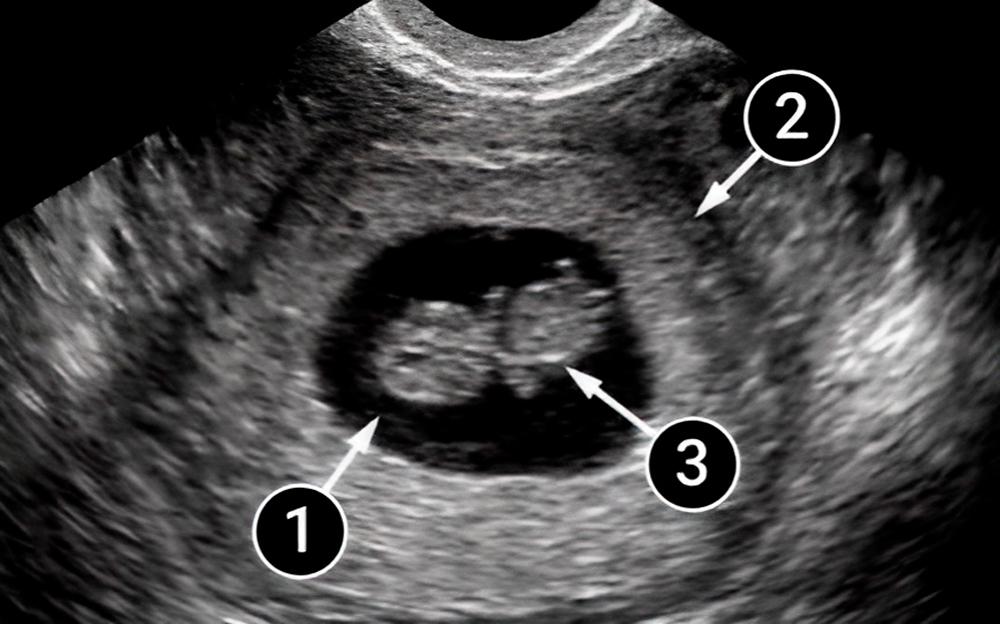

Lo que podemos ver en un ultrasonido

En esta foto, se delinea el contorno del creciente útero. El bebé aparece como un pequeño renacuajo flotando en el líquido amniótico. El cerebro aparece como dos puntos blancos, que crecerán hacia los hemisferios derecho e izquierdo. Los pequeños puntos blancos en la parte superior e inferior son el comienzo de los brazos y las piernas del bebé.

La pequeña mancha oscura es el corazón en desarrollo del bebé.

saco amniótico

útero

embrión